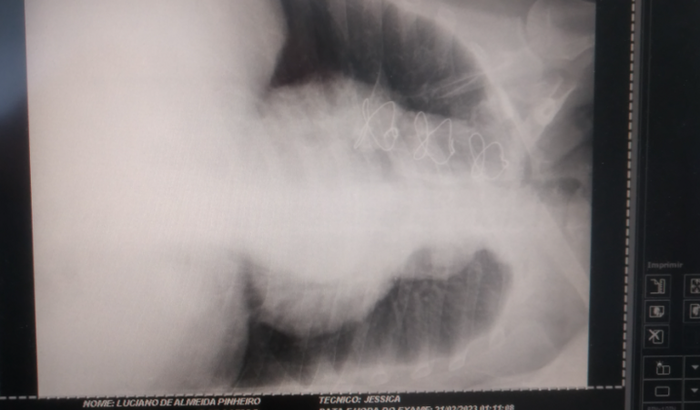

Olá, me chamo Luciano (o baiano/ Lumacky) me ajudem a manter meu coração vivo, pois estou enfrentando muitas dificuldades para respirar, andar, dormir, caminhar. Eu praticava exercícios físicos, mas por conta disso tudo, eu tive que abandonar o que eu mais gostava ( esportes) Tenho uma cirurgia na válvula mitral (valvoplastia/ ICC/ problemas circulatórios) Estou a mais de 1 mês sem conseguir dormir, devido a insuficiência respiratória, e eu estou a mais de 6 meses aguardando por uma vaga para passar em consultas com a cardiologista e fazer exames, tudo isso depende do SUS, via Cross! E para mim continuar mantendo meu coração vivo, preciso da ajuda de todos vocês! Que Deus abençoe todos